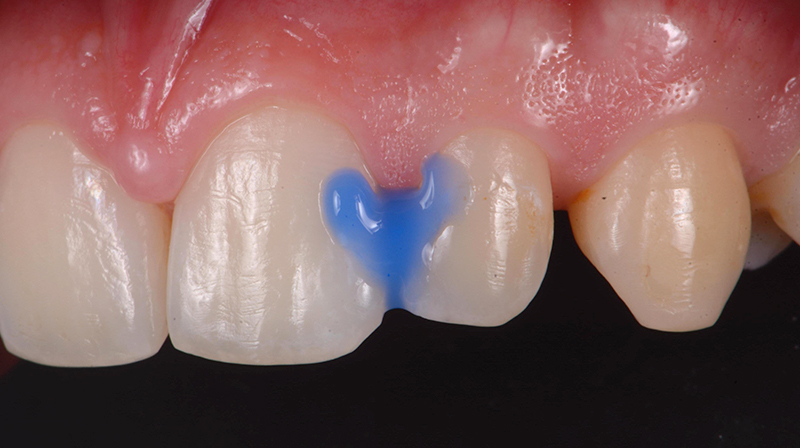

Prima dell’applicazione, è fondamentale detergere accuratamente la superficie dentale al fine di rimuovere la pellicola acquisita mediante ipoclorito di sodio al 2% per 20 secondi e quindi risciacquare e asciugare (Fig. 1). Successivamente è necessario rimuovere eventuali depositi inorganici, mordenzando con Acido Ortofosforico al 35-37% per 20 secondi. Una volta terminato, aspirare e risciacquare (Fig. 2).

Fig. 1 - Rimozione della pellicola organica acquisita con Ipoclorito di sodio al 2% (Da: G. Sammarco. Cariologia Clinica. Quintessence publishing Italia, 2025).

Fig. 2 - Mordenzatura con Acido Ortofosforico al 35-37% (Da: G. Sammarco. Cariologia Clinica. Quintessence publishing Italia, 2025).